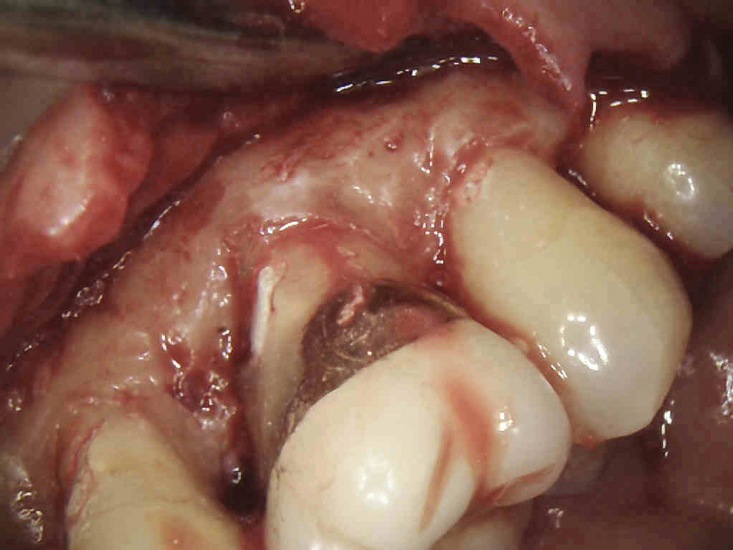

(3.) The initial surgical exposure revealed defects coronal to the crestal bone that were filled with granulation tissue and consistent with ECR.

Figure 3